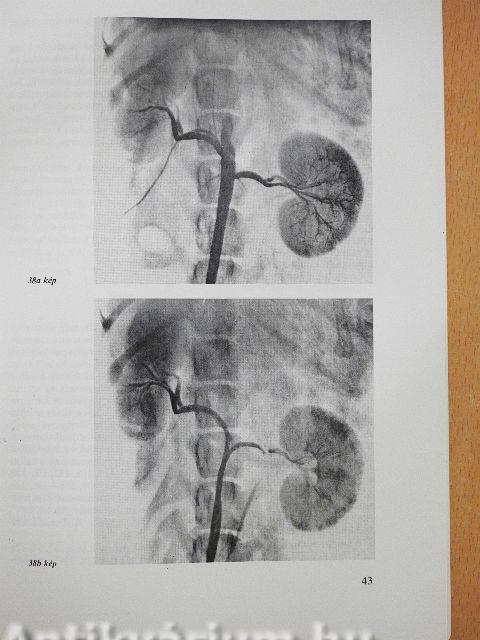

Farmakoangiográfia a daganatok kórismézésében

Farmakoangiográfia első évtizede a vesetumorok diagnosztikájában13

Farmakoangiográfia Vx2 vesecarcinomában64

Klinikánk humán vesetumor anyagának farmakoangiográfiás eredményei97